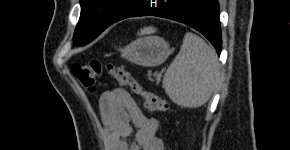

Мультиспиральная компьютерная томография селезенки – высокоинформативный инструментальный метод исследования, основанный на использовании рентгеновского излучения и позволяющий детально визуализировать паренхиму селезенки, состояние близлежащих органов и тканей, питающих ее кровеносных сосудов и лимфоузлов.

МСКТ селезенки проводится как с использованием контраста, так и без него. Контрастирование применяется для выявления патологических очагов, которые могут быть не видны при нативном исследовании. Для этого внутривенно вводится контрастный препарат, содержащий йод и накапливающийся в патологических очагах опухолевой и воспалительной природы.

Нативная КТ (бесконтрастное исследование селезенки) показывает структуру органа достаточно однородно, без выявления незначительных изменений. Для большей информативности делают КТ селезенки с применением контрастных веществ.

На томограмме можно увидеть:

- нарушение целостности селезенки;

- кисты и крупные опухоли;

- кальцинаты;

- травматические и посттравматические изменения селезенки

- кровоизлияния внутрь брюшной полости

- отклонения от нормальных размеров.

- дополнительные дольки селезенки.